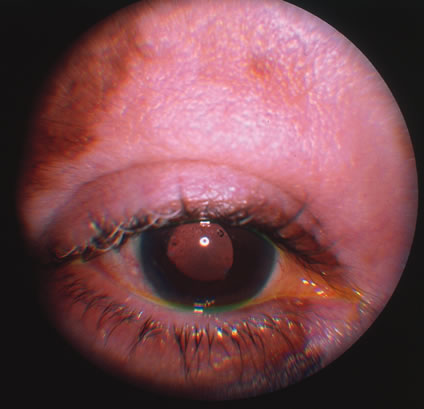

Clinical diagnosis of HSV infection can be made when the characteristic vesicular lesions are present. The diagnosis can be confirmed by isolation of the virus in tissue culture when necessary. Scraping the base of the lesions and Wright's, Giemsa, or Papanicolaou's stains will demonstrate the characteristic giant cells or intranuclear inclusions of herpesvirus infection. Most infections with HSV are mild or asymptomatic and require no specific treatment; however, antiviral therapy can be life saving in cases of neonatal herpes, disseminated infections, and herpes encephalitis. Famciclovir and valacyclovir effective in reducing the pain, healing time, and duration of viral shedding in patients with first episode genital herpes and significantly shortens the clinical and virologic course in recurrent episodes. Immunocompromised patients with chronic progressive oral herpes have also demonstrated improved healing times and decreased viral shedding when treated with oral antivirals.4 Intravenous acyclovir is the drug of choice in the treatment of neonatal herpes infections and herpes encephalitis. The corneal scarring caused by recurrent infection with HSV may be visually disabling and may require corneal transplantation. Over the course of the last decade, the Herpetic Eye Disease Study Group (HEDS) examined the short-term and long-term effects of oral acyclovir and topical steroids on epithelial keratitis, stromal keratitis and iritis. Long-term oral acyclovir was shown to reduce the rate of recurrent HSV epithelial keratitis and stromal keratitis, especially in those who have had multiple prior episodes of stromal keratitis.5,6 Topical steroids are beneficial in preventing progression of stromal inflammation and shortening duration of stromal keratitis. Topical steroids should be given in conjunction with topical Viroptic (King Pharmaceuticals, Bristol, TN) in those with stromal disease or disciform keratitis, but steroids should be avoided in those with epithelial disease. The HEDS trial showed a beneficial trend in the treatment of anterior herpetic uveitis with oral acyclovir, but the trend failed to reach statistical significance.7 Nevertheless, practitioners routinely use oral acyclovir in addition to topical steroids plus a cycloplegic for herpetic-related uveitis. Topical steroids are often difficult to discontinue and many patients require low-dose therapy for an indefinite amount of time. VARICELLA AND HERPES ZOSTER Varicella zoster virus (VZV) is an enveloped DNA-containing virus that is morphologically indistinguishable from other members of the herpesvirus family. Varicella is the primary infection. It usually occurs in children and is characterized by a generalized vesicular rash (chickenpox) with insignificant systemic manifestations. Herpes zoster is a reactivation of VZV in adults resulting in a dermatomal eruption of vesicles (shingles) which is usually accompanied by pain in the affected nerve distribution.8 Varicella occurs most commonly in the late winter and early spring. The highest attack rate is in the 2- to 8-year-old group. The infection is highly contagious and is presumably transmitted through direct person-to-person contact or by respiratory droplets. Approximately 96% of susceptible children will develop the disease within 1 month of exposure to the index case. Herpes zoster infections are seen in patients of all ages and occur with equal frequency throughout the year. Almost all infections occur with a history of prior exposure and are believed to be the result of reactivation of latent virus. The incidence of herpes zoster increases with age and is greater in immunocompromised persons. Varicella usually begins 2 weeks after exposure to a preexisting case. There may be a short prodromal period before the rash develops marked by fever, headache, malaise, and lethargy. The exanthem usually starts on the scalp and the trunk and first appears as erythematous macules that progress to papules and then vesiculate. The lesions remain infectious until they crust over, which occurs in approximately 1 week. Successive crops of new lesions appear so that all stages and sizes of lesions may be present at the same time. Mucosal surfaces in the mouth and conjunctiva may be involved as well. The active course of an uncomplicated case is usually over in 7 to 10 days after which the virus remains in a latent state within the dorsal root ganglion of the sensory nerves. In the majority of cases of herpes zoster, pain and paresthesias precede the skin eruption by several days. The skin lesions morphologically resemble those of varicella; however, they tend to be larger and more bullous. The lesions conform to dermatomal distributions and do not cross the midline. The thoracic nerves are most frequently involved followed by the trigeminal and cervical nerves. Herpes zoster occurs more commonly in patients with impaired immunity such as those with neoplastic disease, particularly lymphoproliferative disease, or human immunodeficiency virus (HIV).9 In uncomplicated herpes zoster the majority of patients younger than 60 will have complete resolution of their pain and skin lesions within 4 weeks. The persistence of pain beyond this point (postherpetic neuraglia) is more common in the elderly population. Most ophthalmic involvement by varicella is mild.10 Pocks on the eyelids and a nonspecific papillary conjunctivitis with a watery discharge are common findings. Foci of inflammatory cells may appear on the bulbar conjunctiva, limbus, or peripheral cornea either during the acute illness or weeks to months afterward. These pock-like lesions often ulcerate and are associated with conjunctival hemorrhage and a mucopurulent discharge containing primarily neutrophils. When on the cornea, they may leave faint superficial scars with neovascularization. Occasionally, varicella can cause a punctate, dendritic, geographic, or disciform keratitis associated with a mild to moderate iridocyclitis. Unusual ocular complications of varicella include necrosis of the eyelids, interstitial keratitis, corneal melting, cataract, and optic neuritis. Congenital infection may result in microphthalmia, cataract, chorioretinitis, microcephaly, deafness, and cardiac abnormalities. Involvement by VZV of the first division of the trigeminal nerve is referred to as herpes zoster ophthalmicus regardless of whether the eye is inflamed (Fig. 5). Eighty-five percent of patients with cutaneous eruptions on the side of the tip or midportion of the nose (Hutchinson's sign) will have ocular involvement. Varicella zoster virus can cause blepharitis, canaliculitis, episcleritis, scleritis, conjunctivitis, keratitis, iridocyclitis, uveitis, retinal vasculitis, retinitis, choroiditis, and optic neuritis. Cataracts and glaucoma are late complications related to the uveitis and long-term use of topical corticosteroid therapy.

Corneal complications occur in the majority of patients with herpes zoster ophthalmicus. A punctate epithelial keratopathy with pseudodendrite formation is the earliest and most common lesion that occurs. Stromal infiltrates, disciform reactions, and rarely interstitial keratitis are also observed. Scarring and contracture of the lid margin often results in trichiasis, distichiasis, entropion, or ectropion. Corneal sensation is reduced, and neurotrophic ulceration, corneal melting, or perforation may ensue. Extraocular muscle involvement with facial paresis has been observed.11 The acute retinal necrosis (ARN) syndrome is most often caused by the herpes zoster virus, although occasionally it may be a result of herpes simplex infection.12 It is typically described in healthy patients although association with immunosuppressed patients has also been described. Granular, nonhemorrhagic areas of retinal necrosis may be observed in the fundus, often rapidly coalescing with resulting blindness often caused by retinal detachment. There is often an associated vasculitis and vitritis. In immunocompromised patients VZV or HSV retinitis may also take the pattern of progressive outer retinal necrosis (PORN) (Fig. 6). PORN differs from ARN in that the former is multifocal, localized to the outer retina, and is less often associated with vasculitis and vitritis.